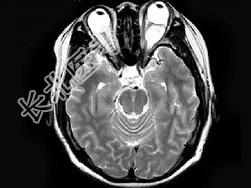

- 单项选择题女,47岁, 左眼球突出伴视力下降半年,MRI平扫及增强扫描见眶内占位性病变, 最可能的诊断是 ( )